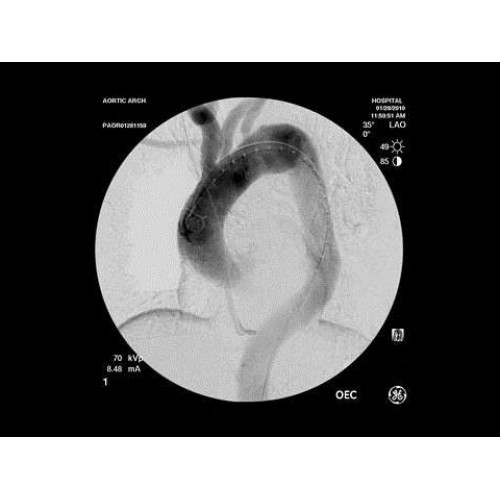

Рентген аппарат GE OEC 9900 Elite

Инновационная мобильная С-дуговая система для интраоперационной визуализации с высоким разрешением. Обеспечивает хирургов качественным изображением в реальном времени при минимальной лучевой нагрузке. Усовершенствованная эргономика позволяет легко позиционировать аппарат в условиях операционной. Поддерживает интеграцию с современными хирургическими навигационными системами.

Передовая рентгенохирургическая система GE OEC 9900 Elite представляет собой инновационное решение для проведения широкого спектра малоинвазивных вмешательств. Это оборудование премиум-класса сочетает высочайшее качество визуализации с интуитивно понятным управлением, устанавливая новые стандарты в области интраоперационной рентгеноскопии.

GE OEC 9900 Elite оснащен революционной системой визуализации, обеспечивающей кристально четкое изображение анатомических структур. Интеллектуальная система автоматически адаптирует параметры исследования под конкретную хирургическую задачу, обеспечивая оптимальный баланс между качеством изображения и лучевой нагрузкой. Особое внимание уделено удобству работы операционной бригады.

• Кардиохирургические вмешательства и ангиопластика

В ведущих медицинских центрах GE OEC 9900 Elite успешно применяется для проведения сложных кардиологических, нейрохирургических и ортопедических вмешательств. Система доказала свою эффективность при выполнении стентирования коронарных артерий, эмболизации сосудов головного мозга и вертебропластики. Многие учреждения отмечают повышение качества операций после внедрения этого оборудования.